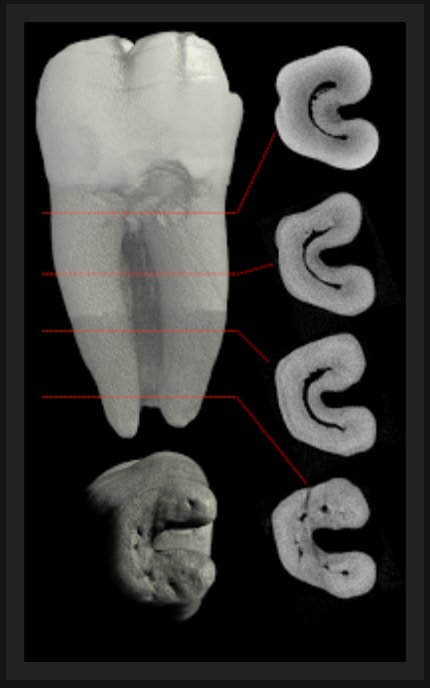

Probable canal en C.

et ptnbz a raison avec cette morpho le canal en c est possible.

Le C c'est la forme de la coupe du canal, ça peut donner l'illusion d'une perfo comme te faire croire que ta perfo est ok ;) ----> locapex

Merci pour la description. Si j'ai bien compris le C peu englober 2 ou 3 canaux avec un 3e canal séparé ou absent.

Si je regarde le plancher de la chambre pulpaire (couple transversale), mon C est relativement peu bombé en forme et va du MV classique au distal excentré en vestibulaire. Le dos du C est vers vestibulaire. N'es-ce pas curieux au vu de la radio pre-op ou l'on voit deux racines mesiale et distal séparées ? Ou bien le C est vraiment très peu profond comme j'en ai l'impression.

Bon après lecture des réponses et réflexion, j'opte (j'espère); soit, le moins probable, pour un canal secondaire de la chambre vers l'espace inter radiculaire, soit, le plus probable pour une anatomie en C donnant l'impression que mon MV est en inter radiculaire (type TIB postée par BURNAX).

Je vais tabler sur une morphologie en c (5 à 7% des 2e molaires mandibulaires) et une imagerie à la "burnax". Le plancher pulpaire ressemble au cas posté par Bill. Un c vestibulaire de distal à mv et un canal individualisé en ml. Dans ce cas le mv peut apparaître dans la furcation à la radio...